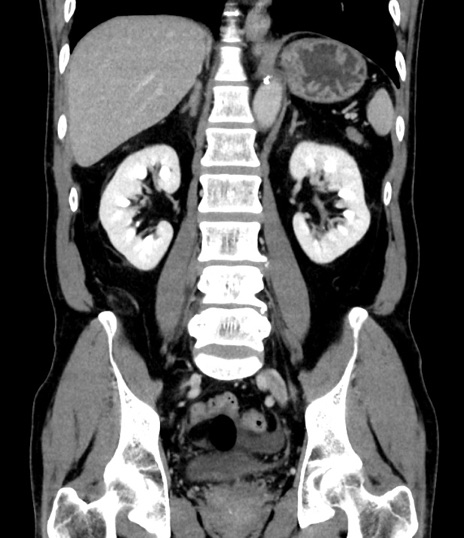

症例8(冠状断像)

【症例】 60歳代男性

【主訴】 黒色吐物

【現病歴】 4日前から嘔気自覚、2日前の朝食後にも嘔気あり、自分で手で嘔吐反射起こし嘔吐したところ血が混ざっていたため受診。

【既往歴】 5年前汎発性腹膜炎を伴う急性虫垂炎で手術、高血圧、前立腺肥大症、高脂血症

【身体所見】 腹部正中に手術癩痕あり 腹部平坦・軟圧痛なし膨満感あり

【データ】WBC 8400、CRP 4.54